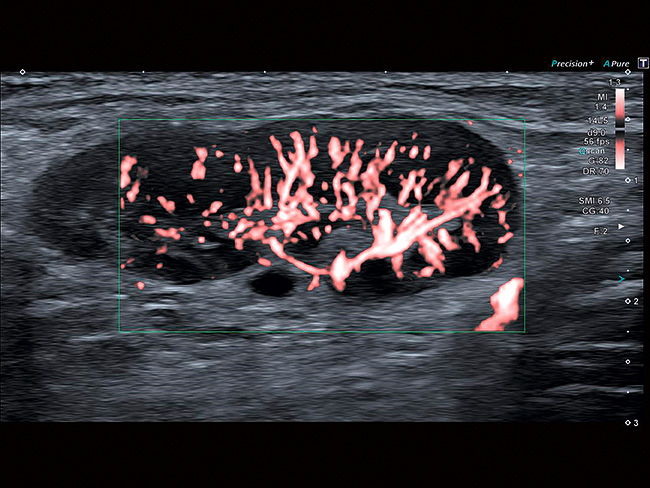

SMI — це технологія, яка розширює діапазон видимого кровотоку та забезпечує візуалізацію низького мікросудинного потоку. За допомогою звичного ультразвукового дослідження така візуалізація раніше була неможлива.

Порівняно зі звичайними доплерівськими технологіями перевагами SMI є висока частота кадрів, висока роздільна здатність, висока чутливість і менше артефактів руху. Це дає клініцистам новий спосіб візуалізувати дрібні судини, що дозволяє більш ефективно та точно поставити діагноз при оцінці уражень, кіст, запальних захворювань та пухлин.

SMI — це потужний та розумний алгоритм, який ефективно відокремлює потокові сигнали від артефактів руху тканин, що накладаються, зберігаючи навіть найтонші компоненти з низьким потоком з незрівнянною деталізацією та визначенням.

SMI аналізує фоновий рух тканин і використовує новий адаптивний алгоритм для виявлення і видалення «фонового шуму» та виявлення справжнього кровотоку.

Це призводить до отримання ультразвукового зображення високої роздільної здатності, на якому можуть бути зображені найдрібніші судин із кровоплином на надмалих швидкостях. Все це можна зробити з високою швидкістю кадрів, що неможливо з будь-якою іншою доплерівською технологією.